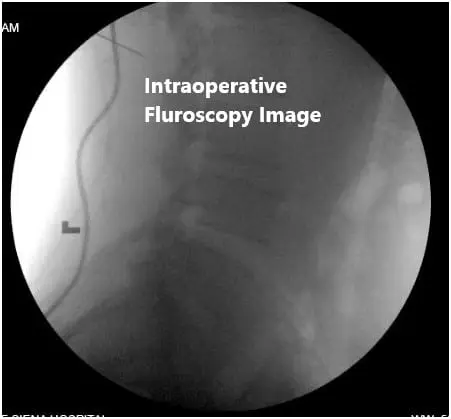

- Use of physician-directed fluoroscopy.

Intraoperative fluoroscopic images